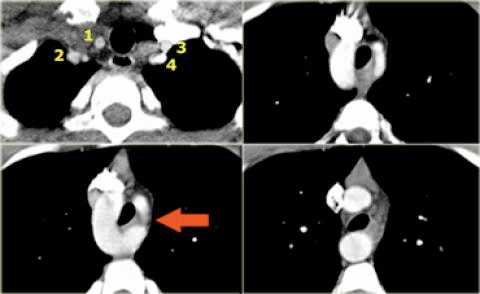

Arteria Lusoria

- Synonyme: Arteria Lusoria

- La plus fréquente des anomalies

- Asymptomatiques ++

- Rarement: Dysphagia Lusoria (compression oesophage)

- Peut faire des diverticules de Kommerell (plus rarement que la gauche aberrante)